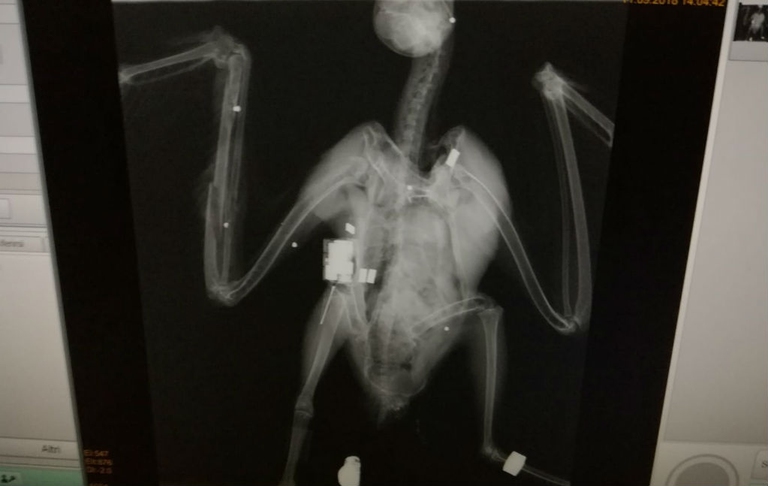

Bracconieri scatenati e dal grilletto facile, quelli che operano in Sicilia. Sembra che in quell’area il bracconaggio sia la regola e ormai si spari a qualsiasi cosa abbia le ali e voli. Ultimo a farne le spese è stato un giovane falco pescatore (Pandion haliaetus) colpito in località Torrenova in provincia di Messina da una fucile a pallettoni. Il rapace è stato soccorso e versa in gravissime condizioni nel centro di recupero del dipartimento sviluppo rurale di Messina, gestito dall’associazione Man. Da quanto si apprende in una nota diffusa dal Wwf, il giovane esemplare era in volo durante la sua prima rotta migratoria.

“Il capovaccaio è un piccolo avvoltoio che in Italia corre il rischio di estinguersi”, scrive il Cerm. “Sono poco più di dieci le coppie che ancora nidificano nel nostro Paese, concentrate in due sole regioni meridionali (Basilicata e Sicilia). Da anni si cerca di sostenere questa popolazione minacciata liberando giovani individui nati in cattività. Clara era equipaggiata con un dispositivo di monitoraggio che consentiva di seguirne costantemente gli spostamenti e conoscerne la precisa localizzazione”. Ma non è servito a proteggerla dai sette pallini di piombo che l’han colpita.